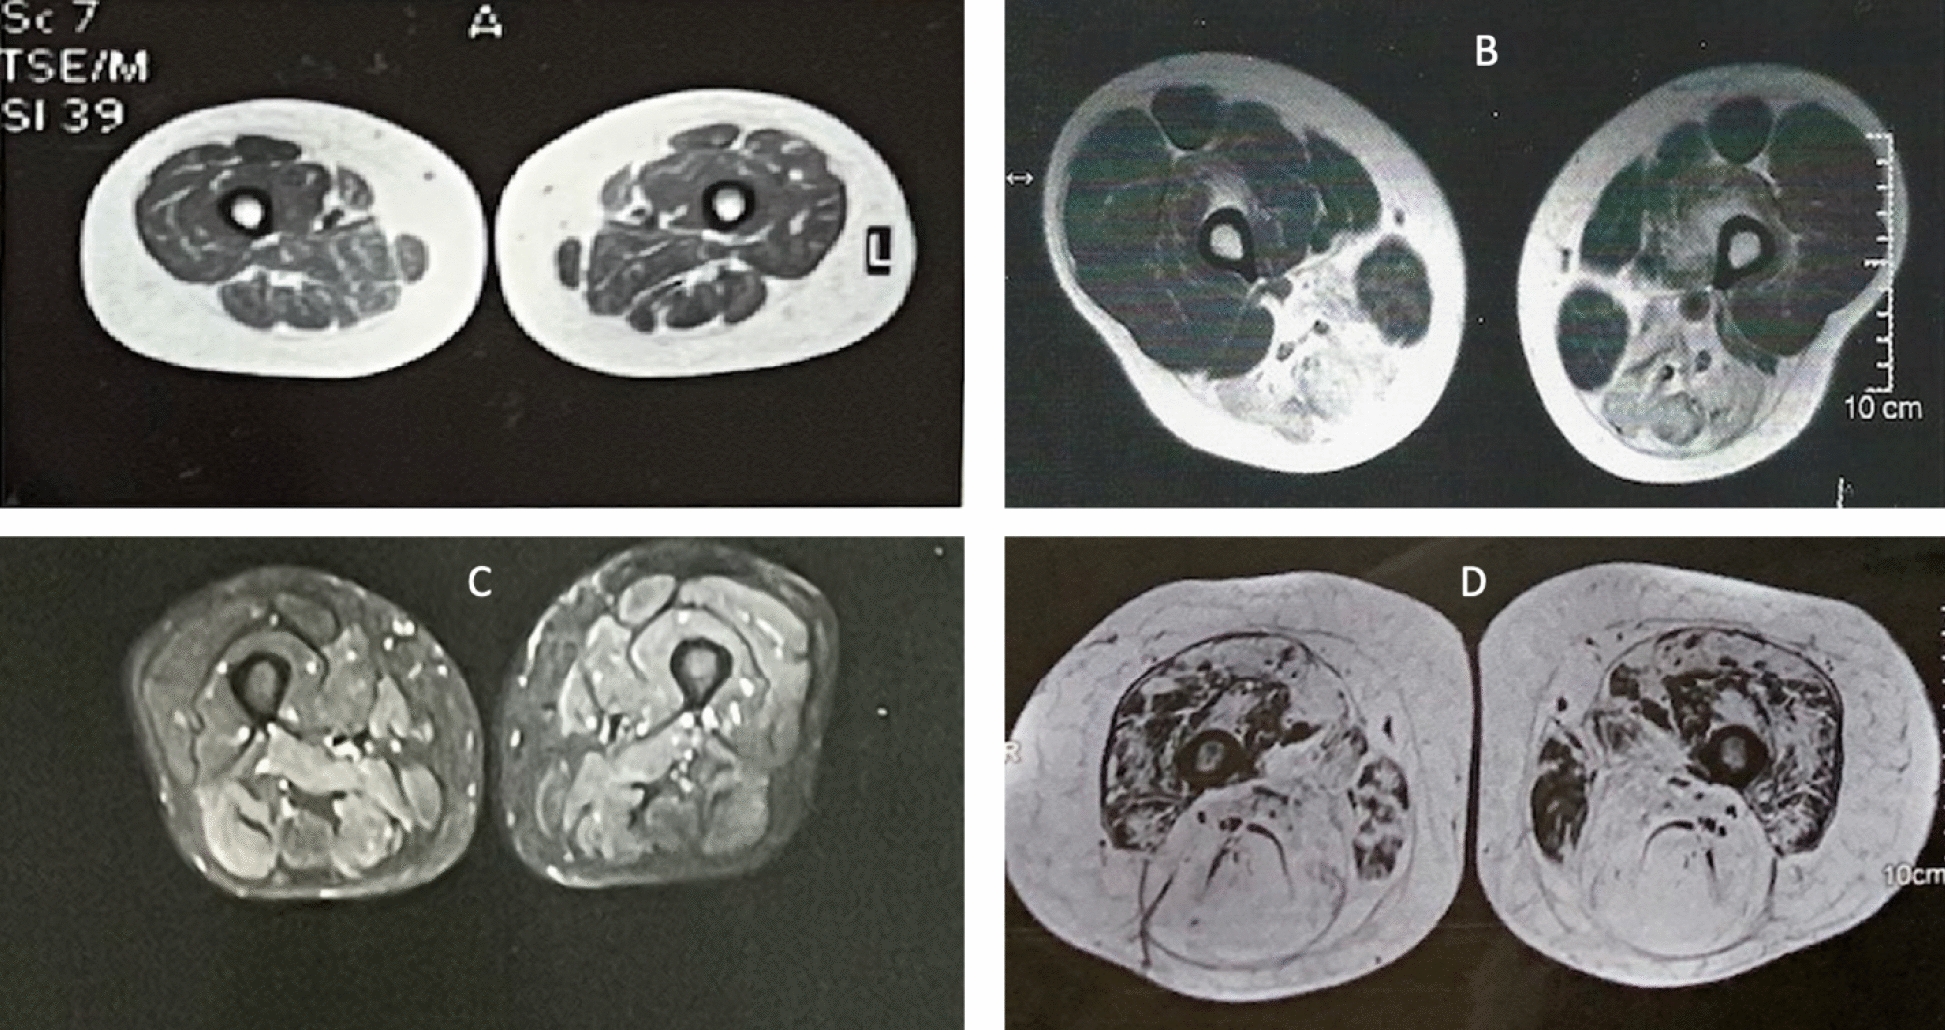

MR images of the different subtypes of patients in our study with different illness durations are shown in Fig. 5.

A Thigh muscle cuts showing mild fat infiltration in a juvenile onset OM patient with 2 years illness history, B Thigh cuts showing hamstrings fat infiltration of an adult patient with OM with 8 years illness duration, C STIR image thigh cut showing edema in an adult patient with positive Anti HMGCR antibody with duration of illness of 1 year, D T1 film thigh cut of an adult with positive anti HMGCR done after 2 years of onset showing fat infiltration in all muscle groups more in posterior muscles.

The MRI findings of our patients who presented within the first year of onset showed normal findings or edema with no fat replacement. Patients who were investigated one year after onset showed variable degrees of muscle fat infiltration (Fig. 4). It has been shown recently that in all types of myositis, including IMNM, fatty replacement can begin early after disease onset, suggesting that early diagnosis and initiation of therapy may help to decrease long-term disability [23] this can be seen in MR images from our study that are shown in Fig. 5. Numerous publications have discussed MRI findings in immune-mediated necrotizing myopathy in relation to muscle involvement and pre- and posttreatment observations. For instance, Mohassel and colleagues (2019) assessed six patients with anti-HMGCR antibodies using MRI before and after treatment to monitor disease remission. Despite these studies, the relationship between the duration of IIM at diagnosis and MRI findings remains poorly documented [32].

Our MRI findings in the IMNM group concurred with the fatty infiltration pattern, but posterior thigh muscles were more frequently affected by edema (Table 4), which partly concurs with the findings of the 255th ENMC workshop (2022) on muscle imaging in IIM, which described a suggested MRI pattern in IMNM as edema involving proximal muscles, including the anterior compartment of thigh muscles, while fatty replacement predominantly affected posterior and medial muscle groups; however, they concluded that there is no distinctive pattern for IMNM [14].